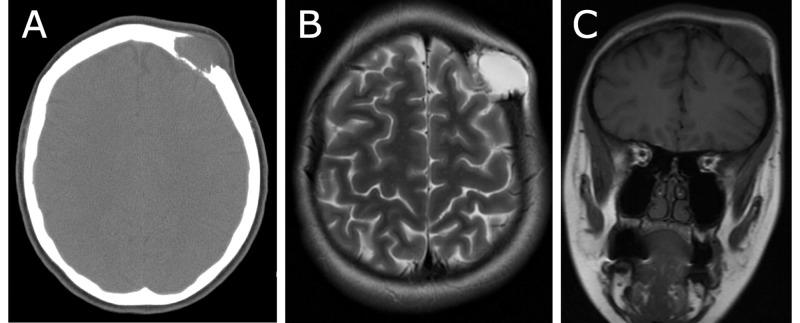

Giant cell tumors are rare benign lesions that typically occur at the epiphyses of long bones in the extremities and present with pain or swelling. These lesions very seldom occur in the skull, where they preferentially affect the sphenoid and temporal bones that develop by endochondral ossification. We report a rare case of a giant cell tumor of the frontal bone and review the literature on these lesions. A 21-year-old woman presented with localized swelling and tenderness over the left frontal bone. Imaging revealed a lytic lesion involving the left frontal bone, which was managed via left frontal craniectomy with resection of the bone and epidural mass. Histopathology revealed a giant cell tumor of bone (GCTB). Most data on giant cell tumors in the skull consist of case reports, with many large series of giant cell tumors having no examples in the skull. This report contributes to the scarce literature on these tumors in the skull.

骨巨细胞瘤是一种罕见的良性病变,通常发生于四肢长骨的骨骺部位,表现为疼痛或肿胀。这些病变极少发生于颅骨,在颅骨中它们更倾向于累及通过软骨内成骨发育而来的蝶骨和颞骨。我们报告一例罕见的额骨骨巨细胞瘤病例,并复习关于这些病变的文献。一名21岁女性患者出现左额骨局部肿胀和压痛。影像学检查显示左额骨有一溶骨性病变,通过左额开颅手术切除骨质及硬膜外肿物进行治疗。组织病理学检查显示为骨巨细胞瘤(GCTB)。关于颅骨骨巨细胞瘤的大多数数据都来自病例报告,许多大型骨巨细胞瘤系列研究中均无颅骨病例。本报告为有关颅骨这些肿瘤的稀少文献增添了内容。